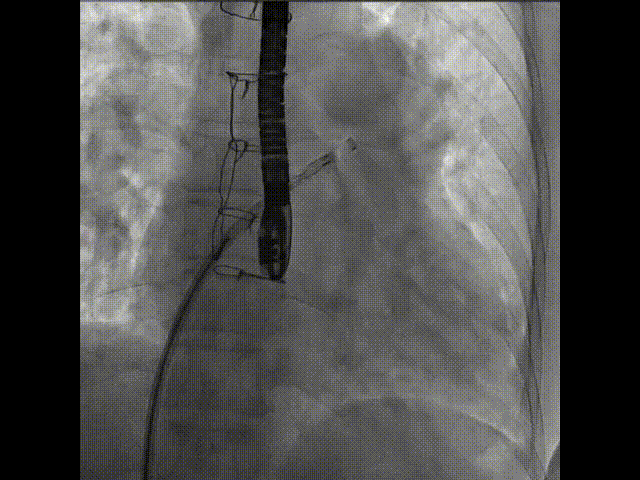

術(shù)中首先在局麻下穿刺股動(dòng)脈、股靜脈,完成心導(dǎo)管檢查評(píng)估后轉(zhuǎn)為全麻,在食道超聲引導(dǎo)下穿刺房間隔,穿刺成功后將加硬導(dǎo)絲送入左上肺靜脈建立軌道,根據(jù)患者病情行球囊預(yù)擴(kuò)張后植入6mm孔徑房間隔造孔支架,經(jīng)透視及食道超聲評(píng)估支架左右盤(pán)展開(kāi)良好,夾持于房間隔兩側(cè),固定穩(wěn)定、位置良好,食道彩超顯示房水平右向左為主分流,分流孔直徑符合預(yù)期大小,心導(dǎo)管檢查評(píng)估達(dá)到預(yù)期效果,釋放造孔支架。術(shù)后12h患者下床活動(dòng),恢復(fù)順利,擬于近日完善術(shù)后評(píng)估后出院。